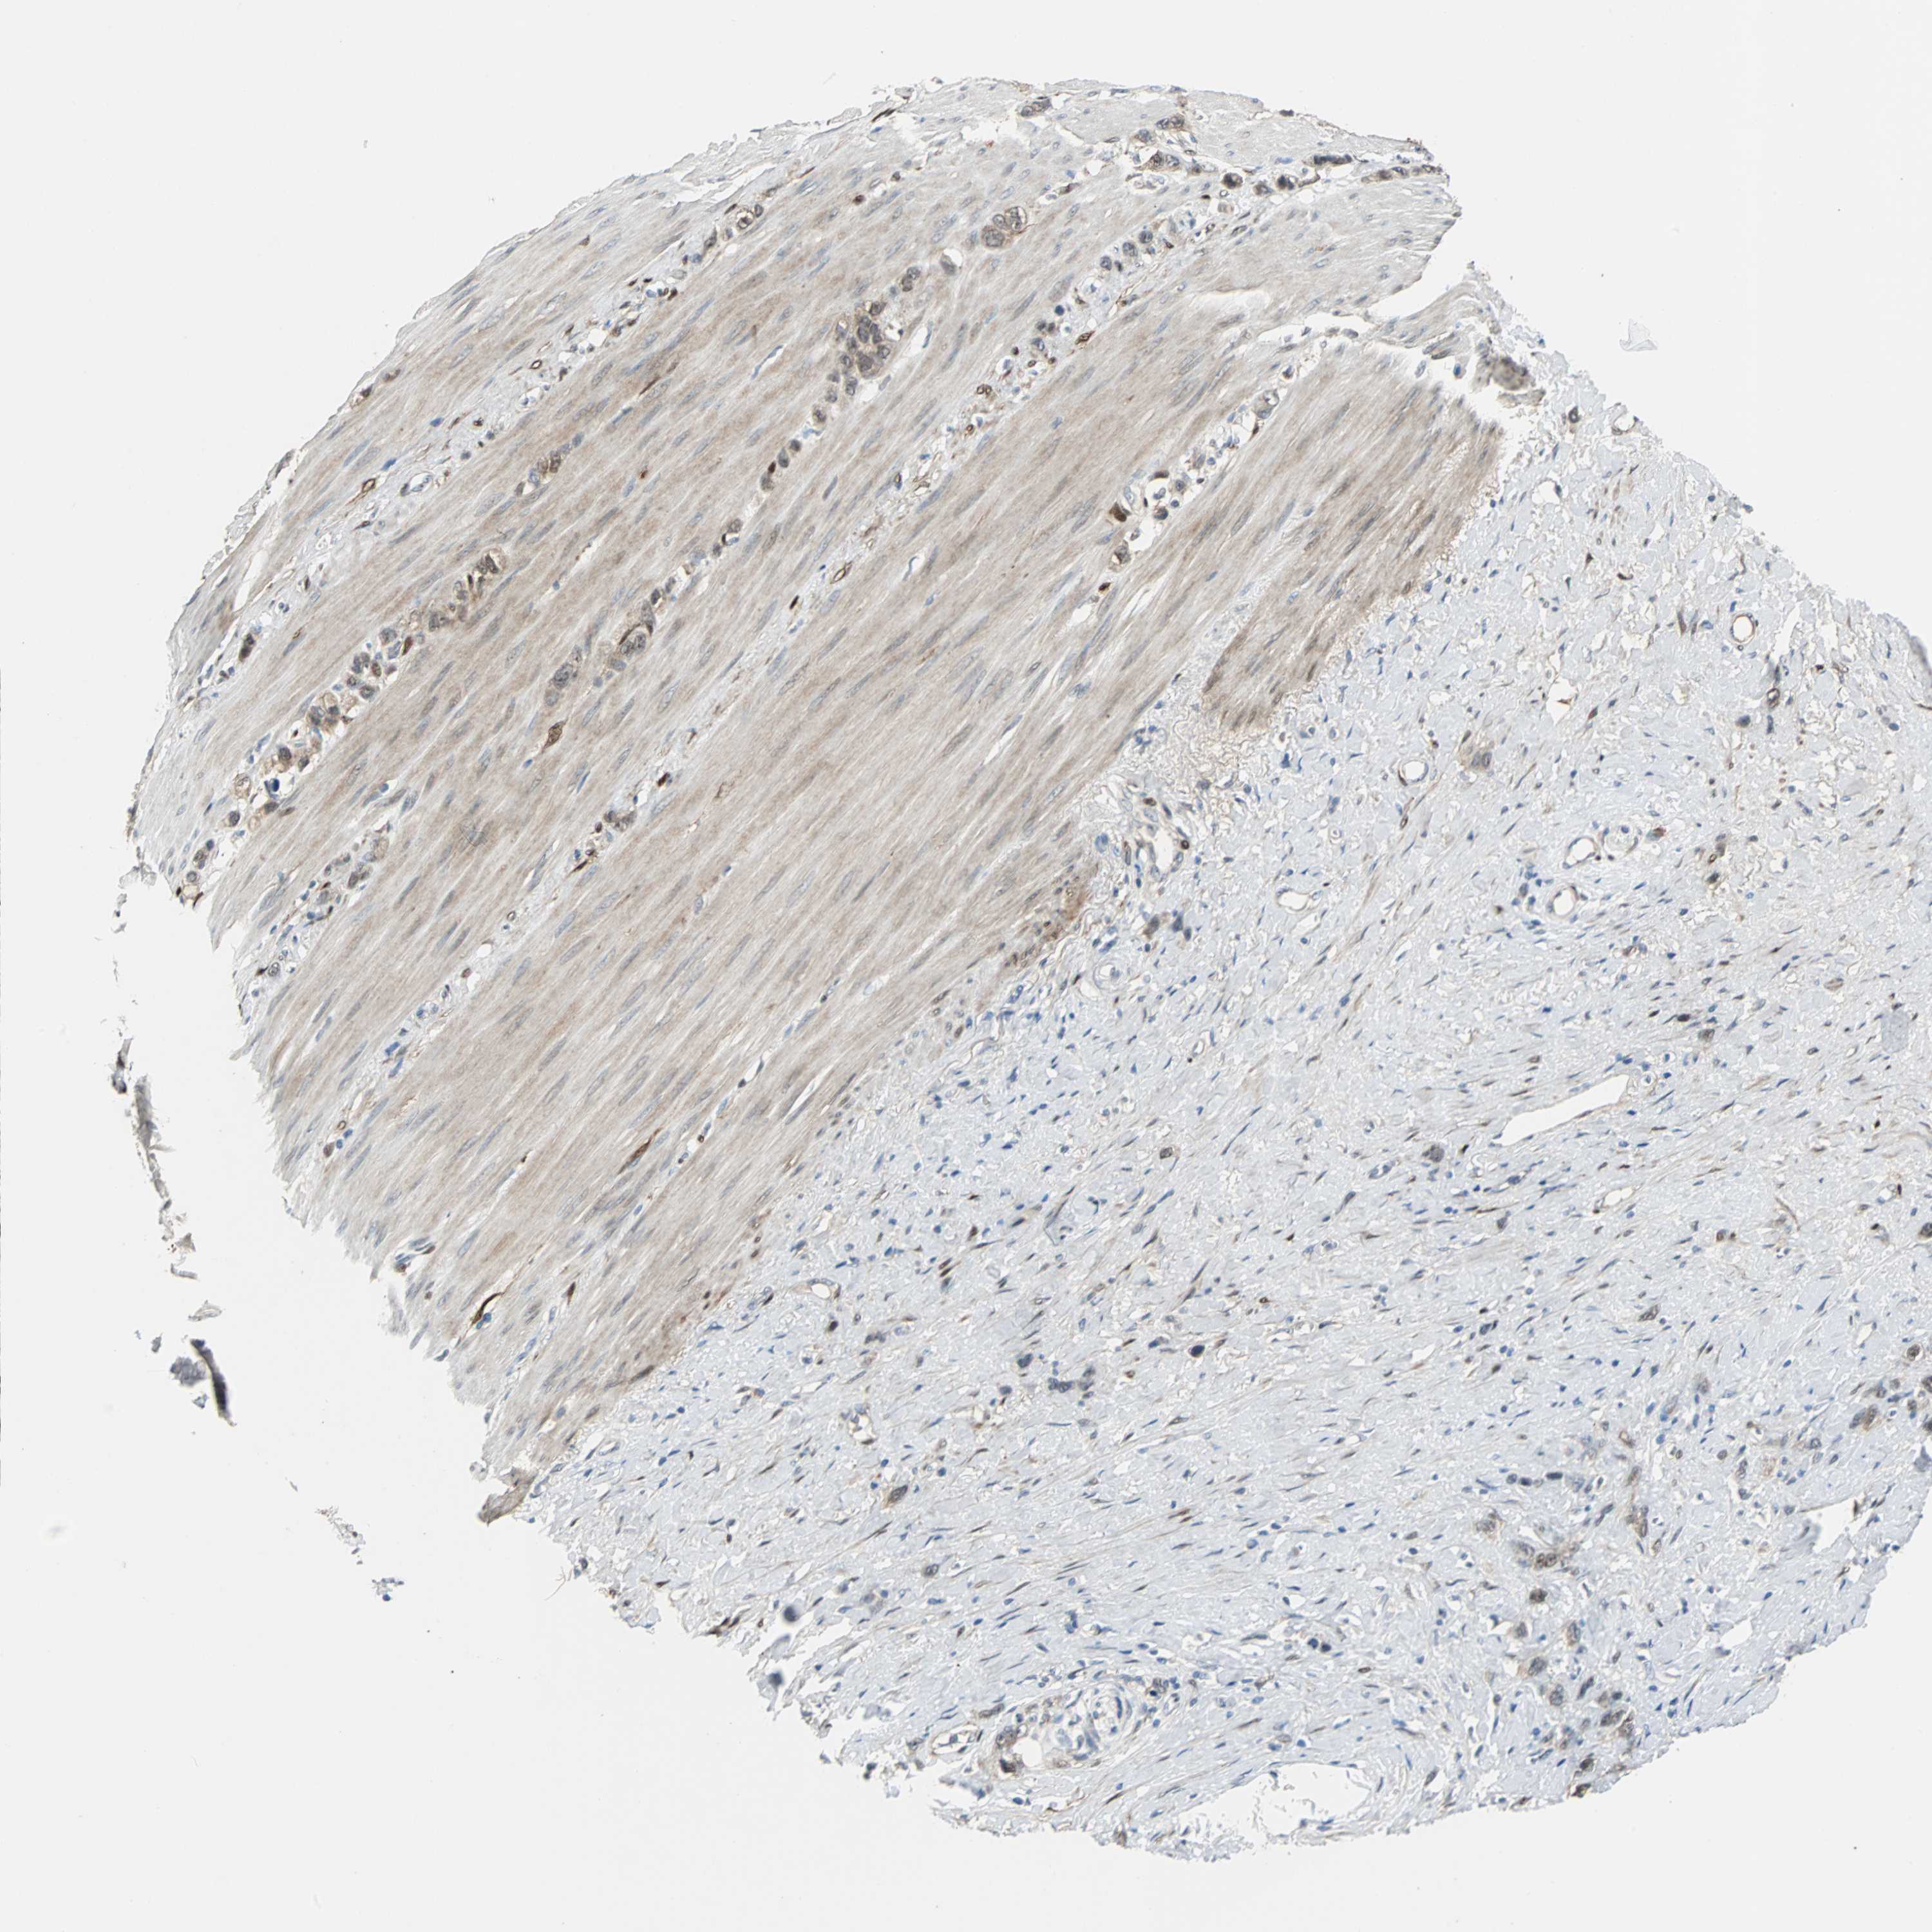

STOMACH CANCER - Protein expressioni

A mouse-over function shows sample information and annotation data. Click on an image to view it in a full screen mode. Samples can be filtered based on level of antibody staining by selecting one or several of the following categories: high, medium, low and not detected. The assay and annotation is described here.

Antibody stainingi

Antibody staining in the annotated cell types in the current human tissue is reported as not detected, low, medium, or high, based on conventional immunohistochemistry profiling in selected tissues. This score is based on the combination of the staining intensity and fraction of stained cells.

Each image is clickable and will lead to virtual microscopy that enables deeper exploration of all samples and also displays staining intensity scores, fraction scores and subcellular localization as well as patient and tissue information for each sample.

Antibody HPA005922

Antibody HPA006028

Antibody CAB008368

Staining

High

Medium

Low

Not detected

Intensity

Strong

Moderate

Weak

Negative

Quantity

>75%

75%-25%

<25%

None

Location

Nuclear

Cytoplasmic/membranous

Cytoplasmic/membranous,nuclear

Adenocarcinoma, NOS

Adenocarcinoma, High grade